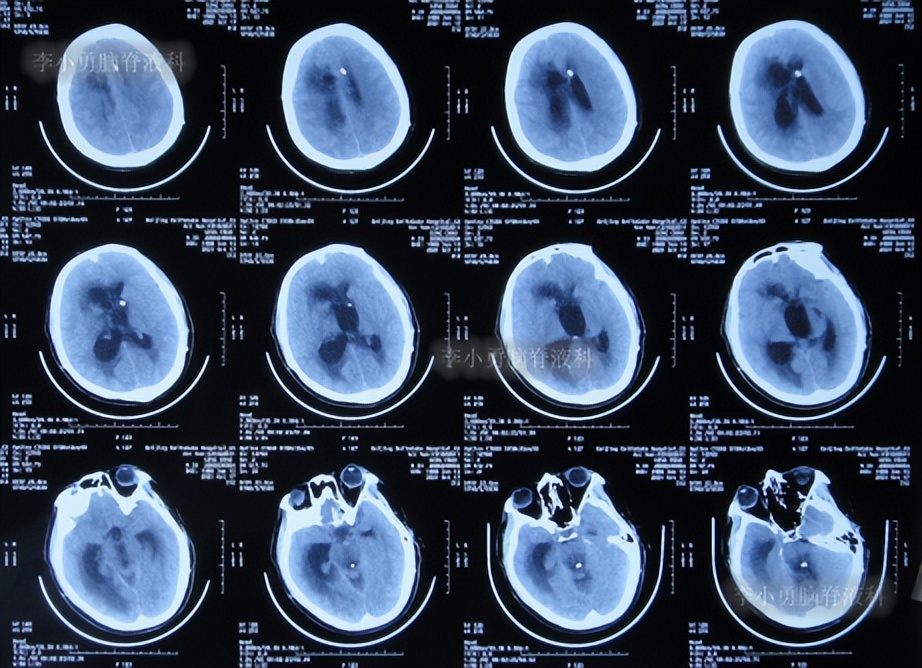

出院后1年半期间,仍时有视物重影的症状,并未给予处理,但到2019年9月27日(脑室腹腔分流术后1年零6个半月),出现头晕,恶心呕吐,视物重影加重,5天后因症状无缓解,就诊于当地的河南省临颍县某医院,查脑CT示脑积水(图-1);给予腰穿检查示颅内压力高220mmH2O。

图-1:2019年10月3日头颅CT